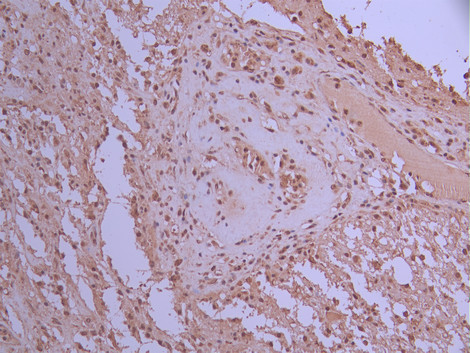

IHC image of CSB-RA796544A0HU diluted at 1:100 and staining in paraffin-embedded human glioma cancer performed on a Leica BondTM system. After dewaxing and hydration, antigen retrieval was mediated by high pressure in a citrate buffer (pH 6.0). Section was blocked with 10% normal goat serum 30min at RT. Then primary antibody (1% BSA) was incubated at 4°C overnight. The primary is detected by a Goat anti-rabbit polymer IgG labeled by HRP and visualized using 0.05% DAB.